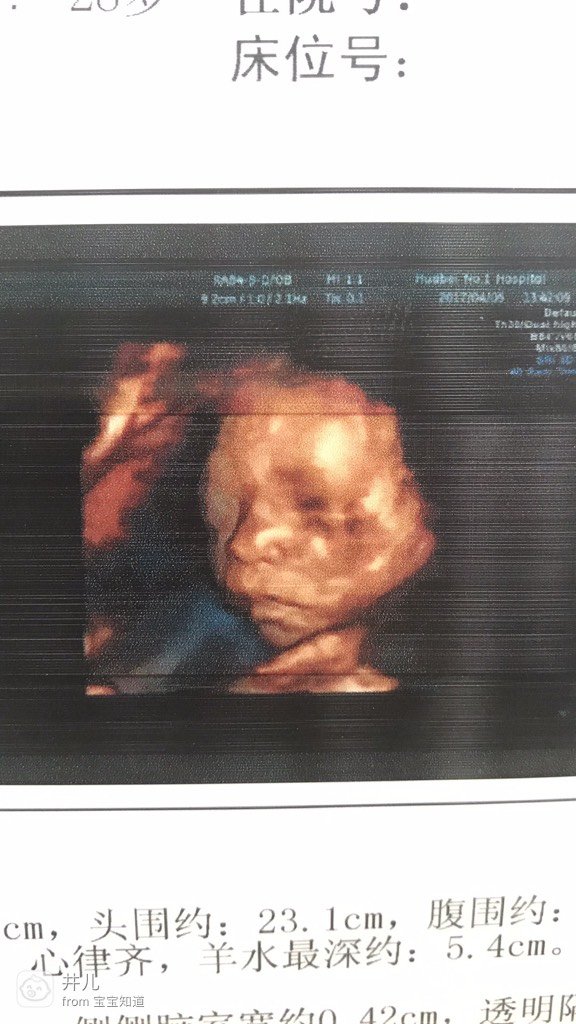

附带本人和宝宝四维图片的侧脸图🙈